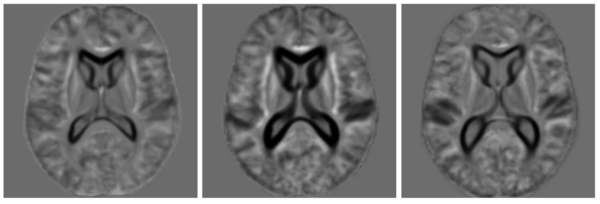

Two templates in a 50 subject MRI.

We spatially normalized all the subjects into \textit{a standard space} using the iCluster algorithm with one-template and a 32x32x32 B-spline transformation model, and explored the alignment of the manual labels for clinical and image-based groupings. For each region of interest, such as amygdala, we computed the modified Haussdorff distance (MHD) in the standard space. MHD is a non -symmetric distance measure between the boundaries of two labels and is zero for perfect alignment.The MHD values for each region of interest were then summed up to obtain a total label distance for each ordered subject pair. The following figure shows the total label distance for all subject pairings under the different groupings. We note that image-based clustering of iCluster (both with two-template and three-template) groups subjects that have better label alignment, whereas the clinical grouping demonstrates no such coherence.

Label Alignment Matrices for the three groupings in the Shenton50 data set.